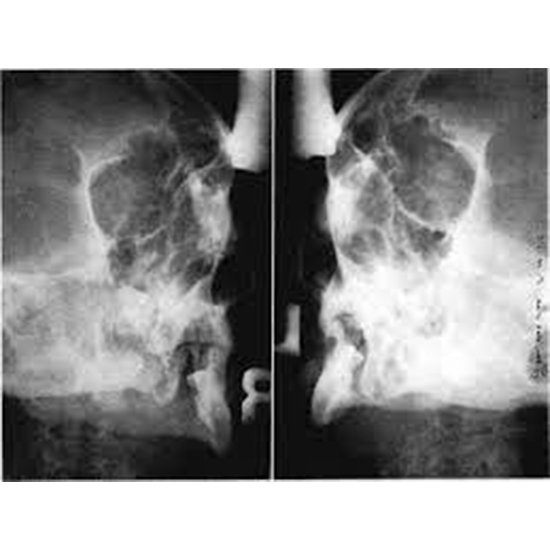

X-RAY OF BOTH OPTIC FORAMEN PROCEDURE

This view is useful in evaluating:

• Orbital foramen

• Orbital wall

• Internal auditory meatus

• Skull fracture

• Paget disease

• Neoplastic change

• Frontal bone

• Ethmoid and frontal sinus

• Structure seen in dental region

• Mastoid sinus

• Sphenoid's bigger and smaller wings

Part positioning

• The patient's nose and forehead are placed on the IR while they are positioned in front of a vertical detector.

• The orbito-meatal line intersects the IR at a straight angle.

• The forehead and nose are both touching the detector

• A petrous ridge is below orbits